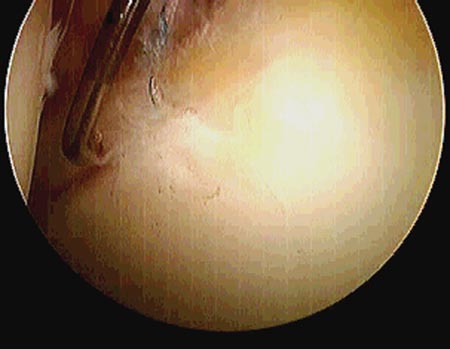

Dentro de las clasificaciones que toman en cuenta la morfología de la lesión mencionamos la enunciada por Lage,18 útil por ser artroscópica, que las divide en (fig. 2, Fig. 3):

Figura 3: Ruptura longitudinal del labrum.